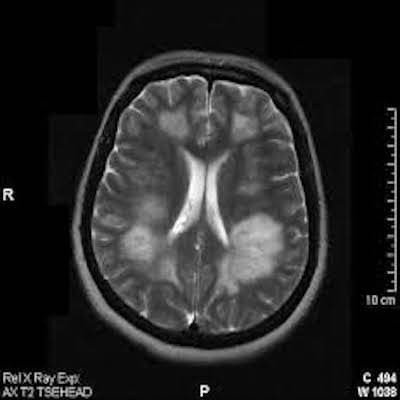

Демиелинизирующие заболевания мозга: МРТ изображения